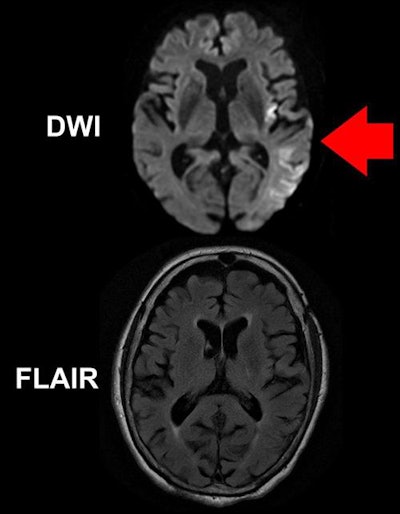

Building on these findings, Schwamm and colleagues assessed stroke progression in 80 patients at 14 U.S. health centers using two MRI protocols: diffusion-weighted imaging (DWI) and fluid-attenuated inversion recovery (FLAIR). The high sensitivity of DWI makes it suitable for detecting changes in blood flow through the brain in the first minutes after stroke onset, whereas FLAIR generally reveals the effect of stroke on the brain after several hours of reduced blood flow.

In 70% of the wake-up stroke patients, the authors observed early reductions in blood flow to the brain on DWI-MRI scans but no noticeable changes on FLAIR MRI scans -- a difference they referred to as quantitative DWI-FLAIR mismatch (qDFM). This mismatch suggested that these patients were still in the early stages of their stroke, meaning that tPA treatment could be a viable option for them.

"Brain tissue that is abnormal on DWI but not yet abnormal on FLAIR has been seen in patients ... four hours or less after known symptom onset," said co-lead author Ona Wu, PhD. "That discrepancy provides a snapshot of tissue evolution as stroke progresses in the first few hours, and that is the pattern we used to select patients for treatment, since they were likely to be similar to patients with known symptom onset who have benefited from tPA."